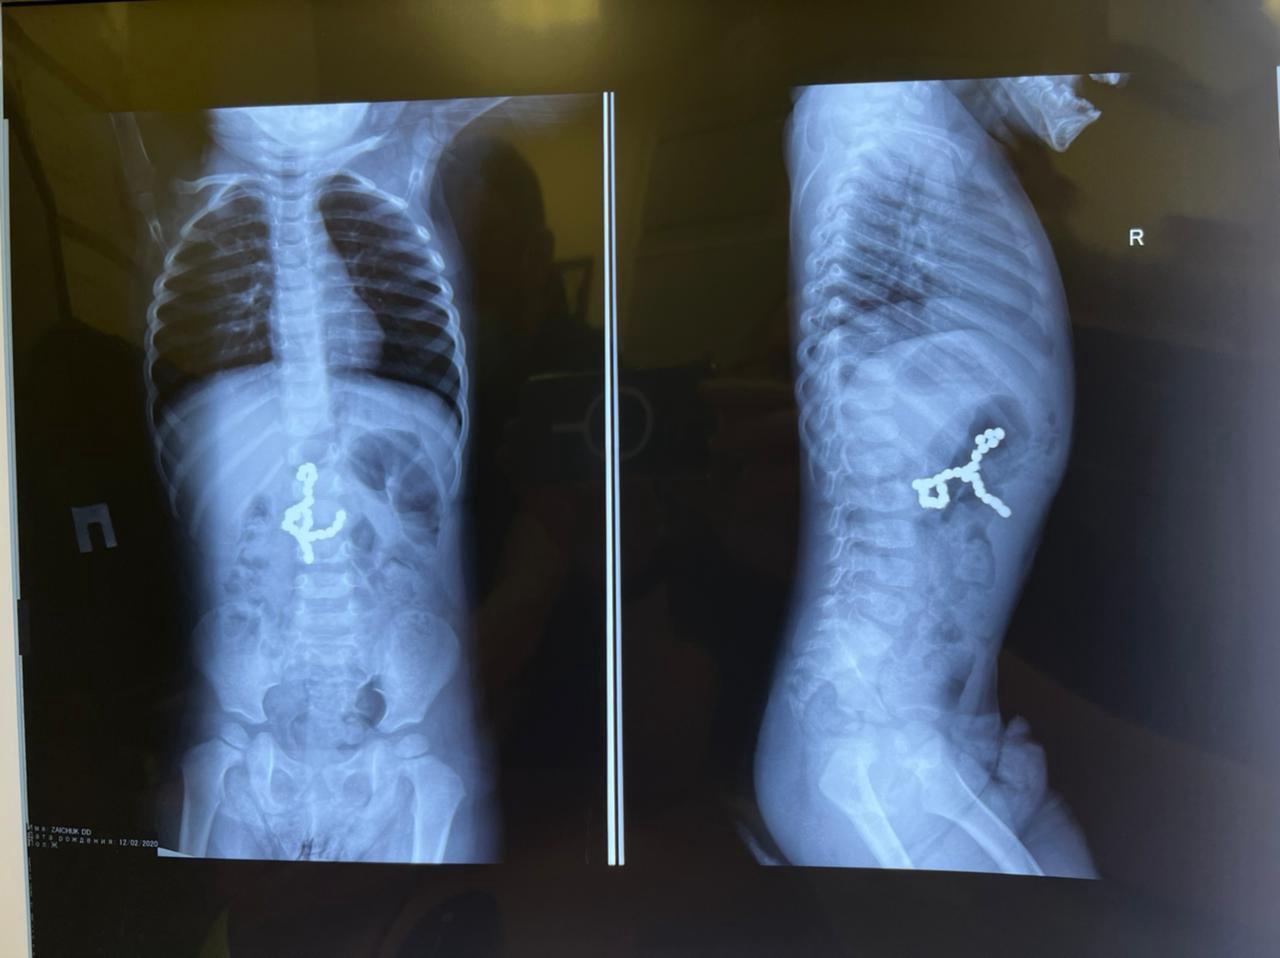

Магнитные шарики на рентгене: Интересные находки

Раздел: Картинки на заметку